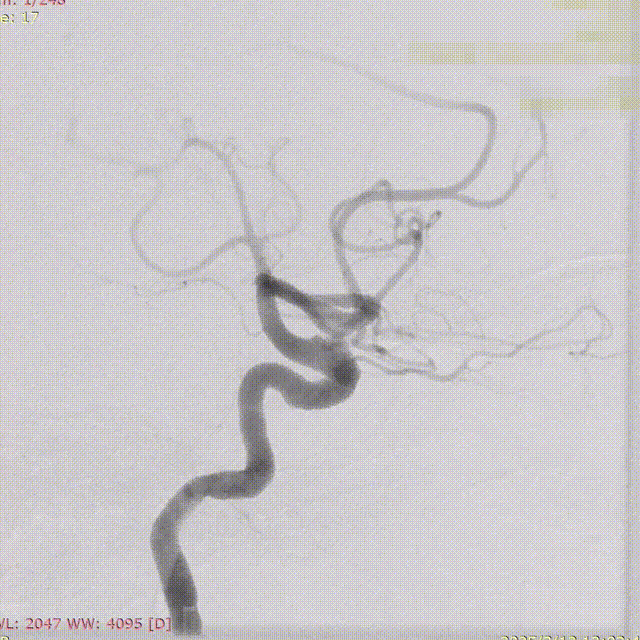

支架及支架微导管到位。

支架头端打开。

支架远端打开造影。

等张释放,支架中段打开至50%释放标记点。

支架中段打开造影。

支架近端打开,完全释放。

支架完全释放造影。

术后即刻造影。

术后重建。